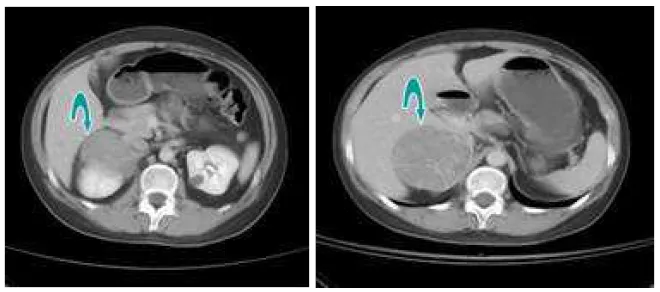

詳解

破題關鍵

這題的解題核心在於結合影像學檢查(電腦斷層)和內分泌檢驗結果(睪固酮、DHEAS)來定位病灶並判斷其性質。圖片中右側腎上腺區塊的巨大腫瘤,加上血中DHEAS濃度異常升高,是診斷的關鍵線索。

選項拆解